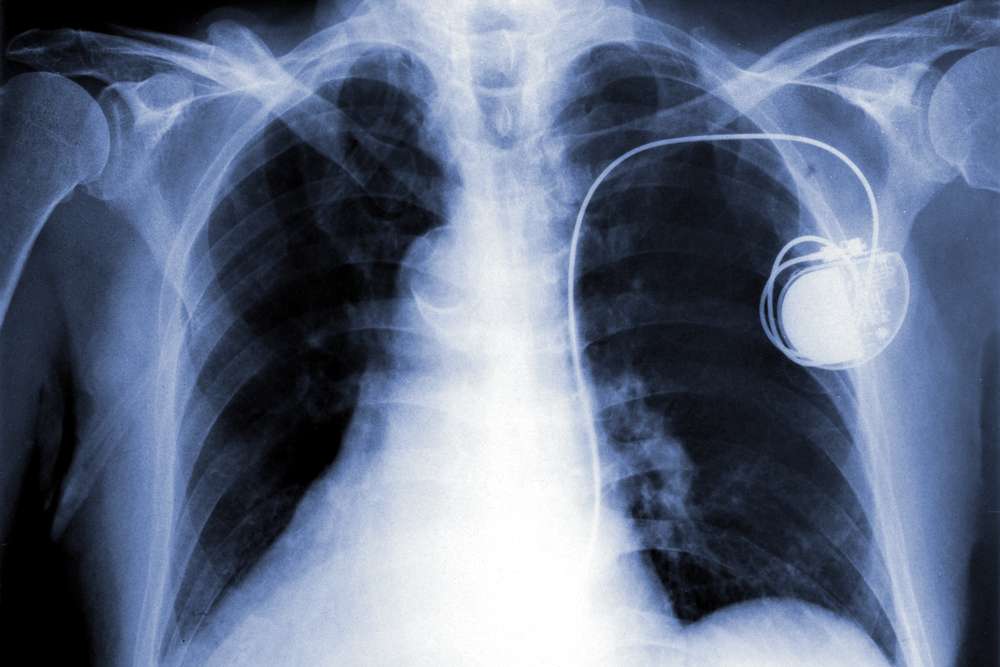

That design is made up of a pocket-watch-sized generator containing a battery, electronics and small computer that is inserted under the skin near the collarbone. The generator is then attached to leads threaded through a vein into the heart. Electrodes on the ends of those leads allow electrical impulses to go to the heart.